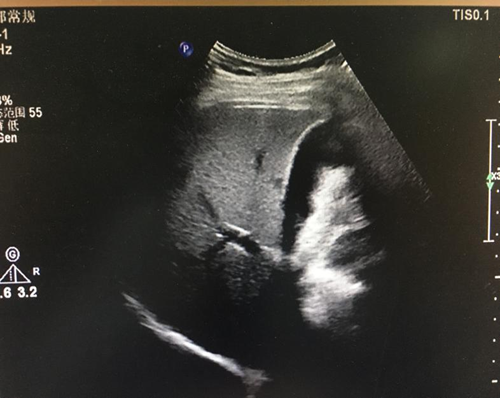

(1)轻、中度脂肪肝:肝大小正常,实质回声均匀、细密、轻度增强,轻度脂肪肝的肝内管道结构清晰,中度脂肪肝的肝内管道结构稍模糊,但仍可辨认清楚,后方回声轻度衰减,深面膈肌可显示。

(2)重度脂肪肝:肝脏体积增大,形态饱满,肝回声均匀、细密、明显增强,肝内管道结构模糊不清,后方回声明显衰减,深面的膈肌显示不清。